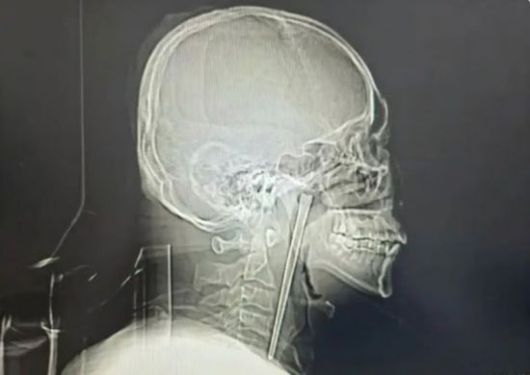

남성의 목에 박힌 금속 젓가락. 바이두 캡처 |

정밀 검사 결과, A씨가 8년 전 삼킨 금속 젓가락은 입천장 뒤에 위치한 목 안쪽 연구개 부위에 박혀 있었다. 다행히 목 주변 점막은 손상되지 않았고, 성대도 정상적으로 기능했다.